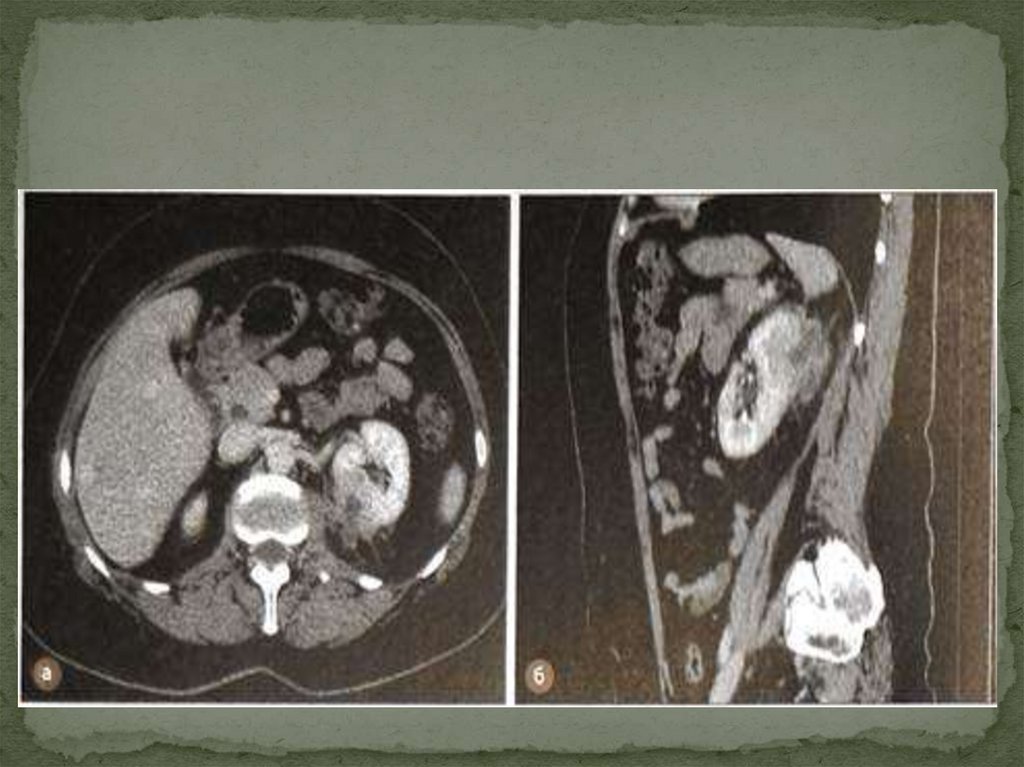

Бел аймағының шолу рентгенограммасында

омыртқаның бел бөлігінде зақымдану жағына

қарай қисаю, анық бүгілу немесе осы жағынан бел

бұлшықетінің контуры жиегінің болмауы жиі

кездеседі. Несепағардың жоғарғы бөлімі жиі сау

жаққа жылжиды. Жедел іріңді паранефритте

құнды ақпарат ультрадыбыстық зерттеу және

компьютерлік томография береді